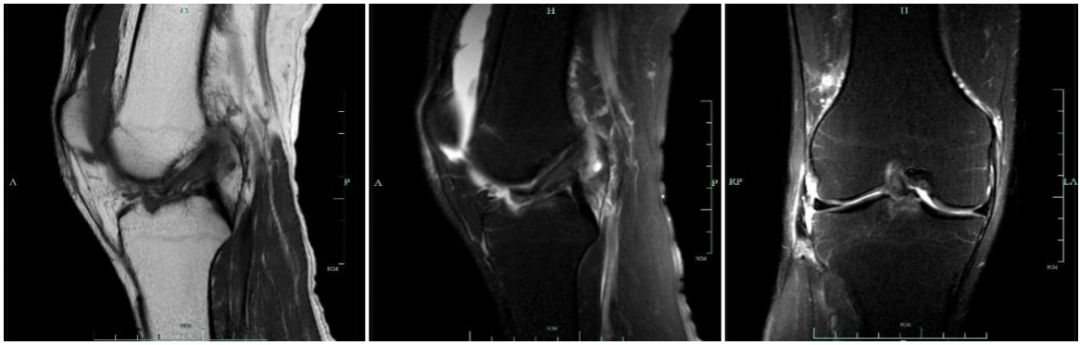

3 级:前交叉韧带完全损伤

在 MR 上表现为韧带信号明显增强,不连续,韧带可能有回缩,韧带走向异常或有假团块等

女,40 岁,外伤 2 周,前交叉韧带胫骨附着部撕脱骨折,胫骨平台骨折,胫骨平台骨折,胫骨见骨折线,伴骨髓水肿,韧带信号明显增强且不连续为 3 级损伤;髌腱远端见高信号改变